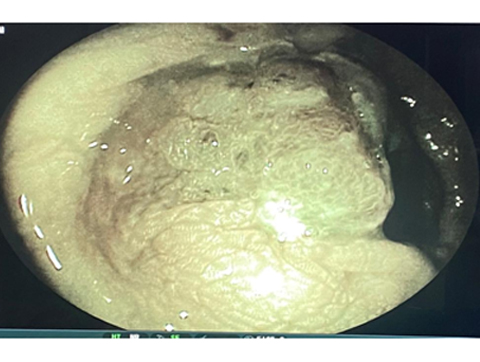

We have state of the art operating theatre with advanced surgical equipments. We have a Karl Storz Spies advanced HD laparoscopy operating system in addition to a 3 chip laparoscopy. We have installed advanced vessel sealing devices like Gen 11 harmonic scalpel, Ligasure from Valley Lab & Argon plasma coagulator. There is a recent addition of Cavitron Ultrasonic Aspirator (CUSA) system into our surgical armamentarium. We have the most recent powered Echelon endo-stapling devices. In addition to all these we have a constant supply of various types of advanced stapling devices for GI surgeries. Our endoscopy machines are having high definition with FICE Technology. Last but not the least we have semi flexible Ureteroscopy for managing common bile duct stones.

HIGH DEFINITION ENDOSCOPY WITH FICE TECHNOLOGY SHOWING A CANCEROUS LESION